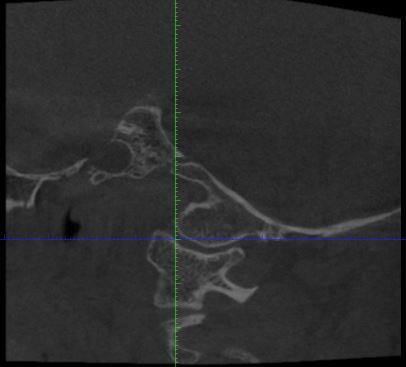

Der HNO Arzt vermutet die Halswirbelsäule als Ursache für den Tinnitus und hat eine DVT anfertigen lassen. Leider kann er die Aufnahmen nicht auswerten und sein Radiologe hat Urlaub. Kann von Euch jemand auf den angehängten Fotos etwas erkennen?

Mann soll die Bilder in 3D anschauen, es ist die ganze datei in dicom format nötig. Einzelne bilder zu schauen ist nutzlos.